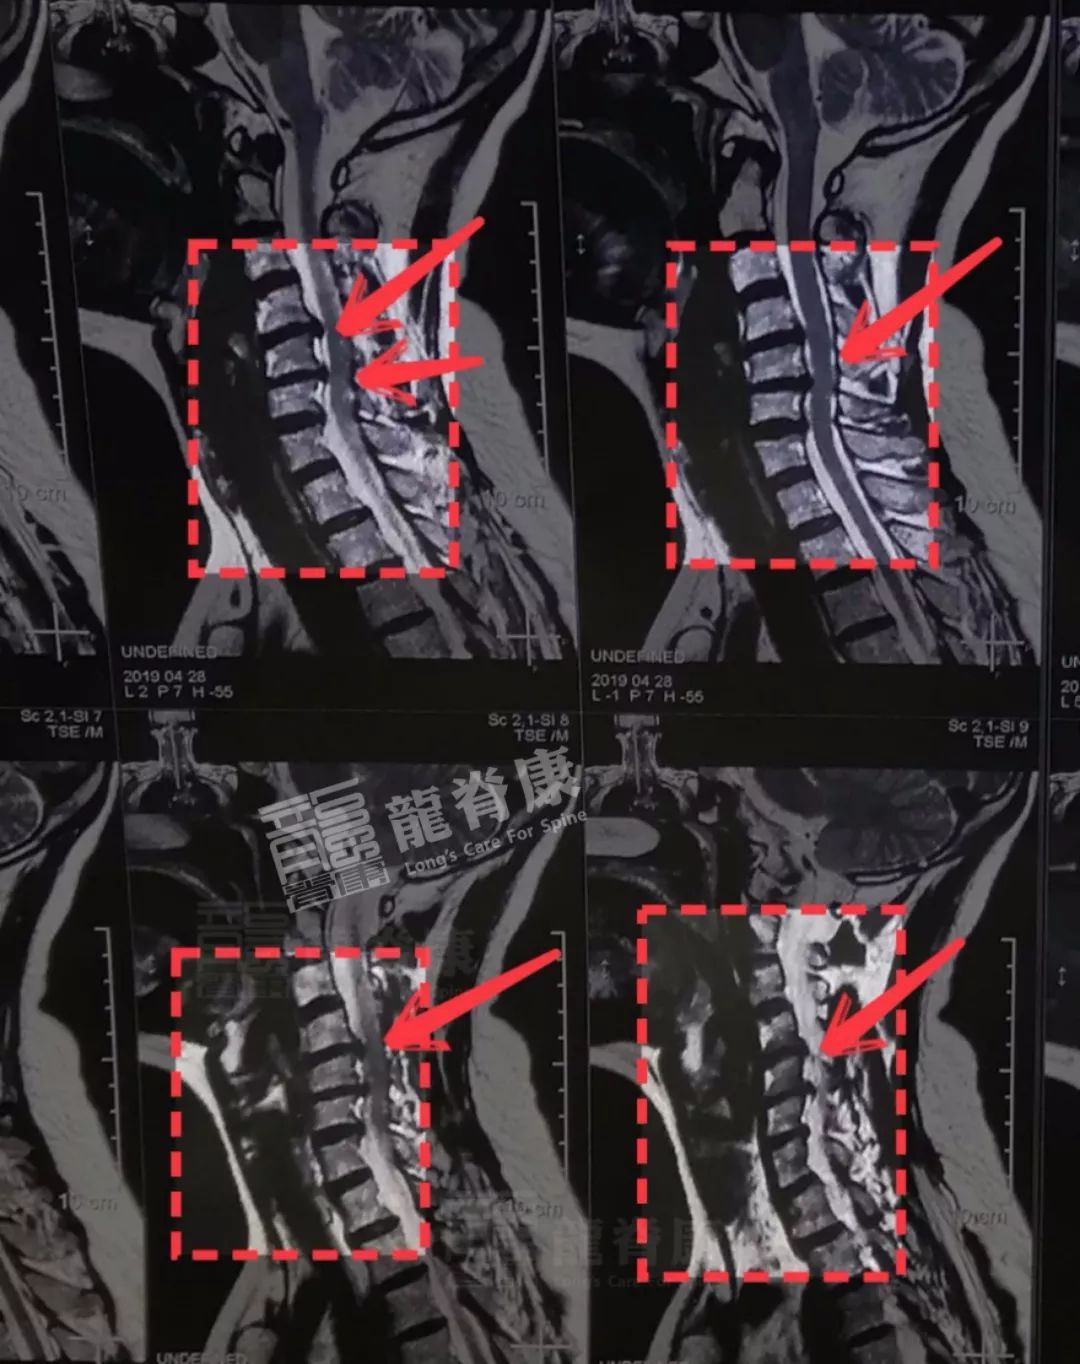

临床上,我们需要进行影像学检查,明确诊断,根据患者的具体情况进而进行治疗。

③ 脊髓型颈椎病有硬膜受压的情况下,椎管内的中枢神经(脊髓)由一层硬膜包裹以起到保护作用,颈椎病变使硬膜及脊髓受压之时应禁止牵引颈椎,以避免更加广泛的压迫和损伤。